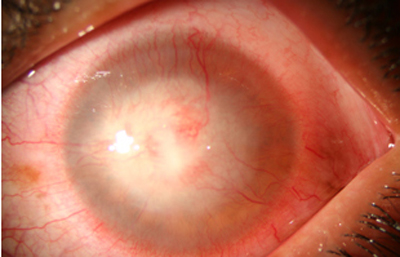

Superficie corneal irregular y grisácea, (Fig. 1, 2) con opácidades granulares en parche y formación de líneas epiteliales elevadas de aspecto granular (Fig. 3), que pueden arborizar dando imágenes de pseudodendritas. Opacidades superficiales satélites. (Figura 4) Inyección ciliar. Ulceración epitelial variante. (Figura 5).

Fig. 1 Síntomas de 15 días evolución

Fig. 2 Síntomas de 25 días evolución

Estas lesiones progresan con la aparición de infiltrados estromales anteriores difusos o focales, (Figura 6) edema circunscrito, y en ocasiones infiltrados en los nervios corneales (Figura 7), (perineuritis, usualmente entre las 1 a 4 semanas de evolución).

En su evolución se observará aumento del edema, agrandamiento y coalescencia de los infiltrados formando un anillo, (Figura 9, 10 y 11) que progresa hacia la formación de un absceso (Figura 12, 13 y 14), queratolisis superficial, adelgazamiento y perforación corneal (Figura 15 y 16).

Limbitis y escleritis anterior difusas.

La vascularización y el hipopion son poco frecuentes en los estadios tempranos de la queratitis. Con el tiempo, en los estados avanzados de invasión estromal, aparecen vasos estromales (Figura 17)